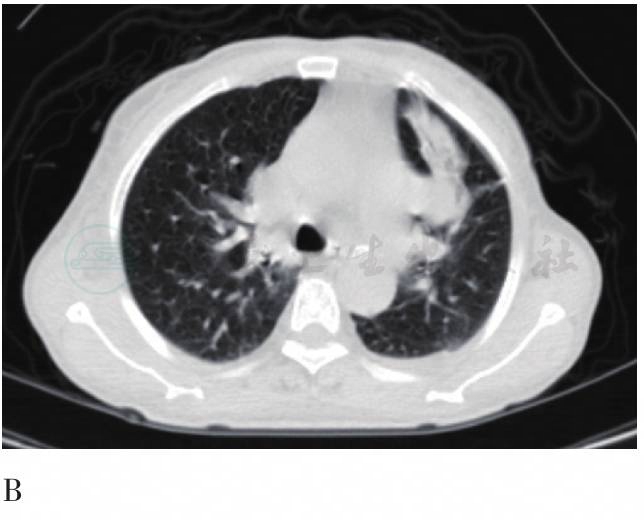

图2 FDG PET/CT胸部横断层图

A、B. CT图像;C、E. PET图像;D. 融合图像。CT平扫:左上肺门纵隔旁结节(2cm×2.5cm),界限清楚,相邻肺组织条片状阻塞性炎症样改变,心包积液、胸腔少量积液。FDG摄取轻度增高,SUVmax为2.0;延迟后SUV无变化